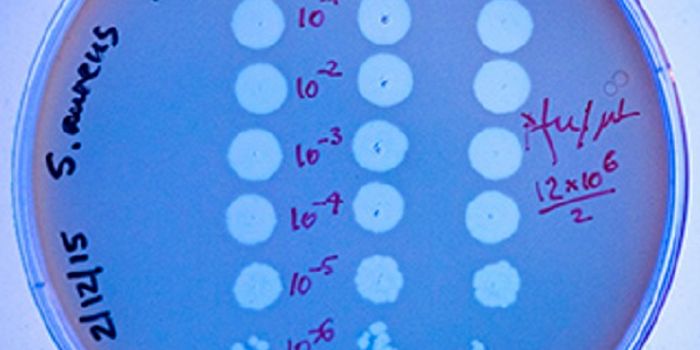

OCT 12, 2016ImmunologyThe key ingredient in the recipe that make staphylococcus and streptococcus infections so dangerous? Superantigen toxins ...